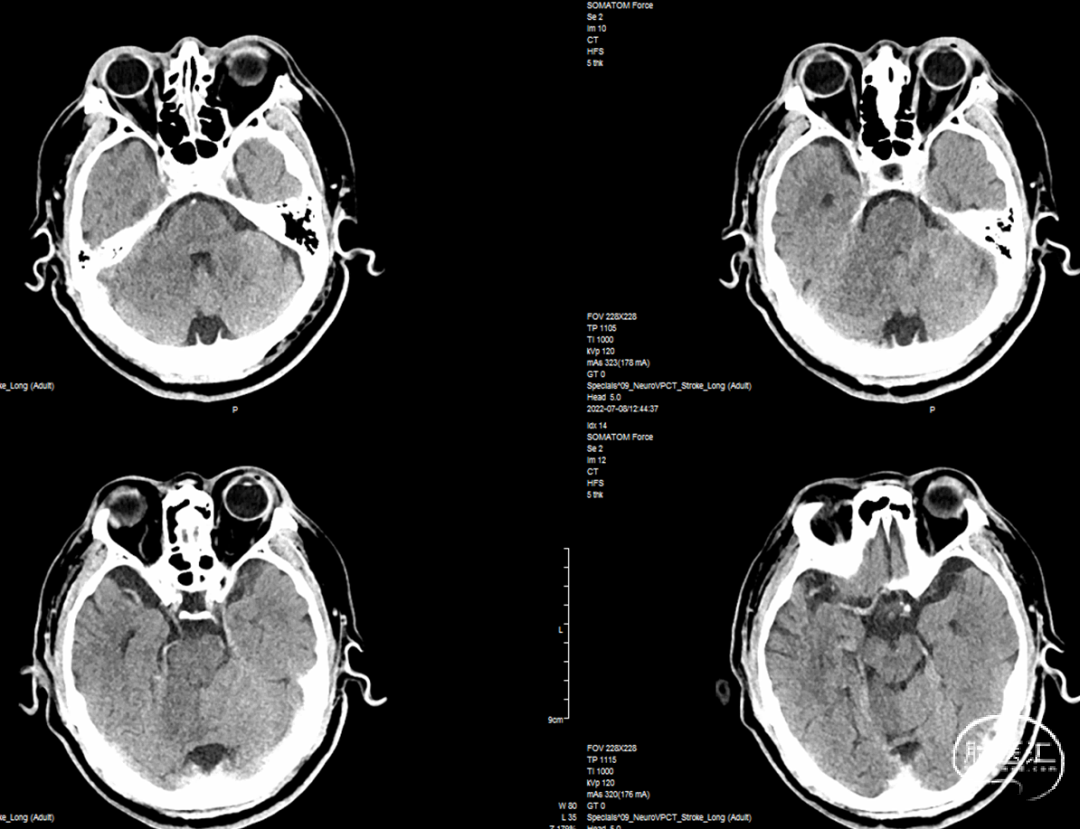

综合术前辅助检查,(Core+pen)/Core=3.58;Pen>15ml;Core<70ml(图3);发病时间小于24小时,存在取栓指征,但是当地医院手术经验告诉我们左侧椎动脉慢性闭塞,且开通异常困难,常规手术方案很难成行,术前制定合理且可行的手术方案至关重要。方案1:仍采用左侧椎动脉+基底动脉取栓的正向开通方案,可能会继续浪费大量时间,甚至最后以失败告终。方案2:采用右侧椎动脉入路,由于右侧椎动脉V4段发育不良,当地医院已尝试过超选,证实无法通过V4段至基底动脉建立取栓通路。方案3:既往有文献报道开颅椎动脉直视下穿刺取栓,虽然方案可行,但我院无类似手术经验,贸然尝试风险难以把控。方案4:回顾当地医院取栓影像资料,发现双侧颈内动脉后交通呈胚胎型,是否可能通过后交通跨循环逆向超选至基底动脉取栓。患者平卧DSA床,全麻插管成功后,用碘伏常规消毒手术区皮肤,铺无菌巾单。取双侧股动脉为穿刺点,于14时00分seldinger法穿刺成功后分别置入8F穿刺鞘和5F 短鞘。行全脑血管造影显示左侧椎动脉起始部闭塞,颈升动脉通过肌支代偿V2及以远的椎动脉血流,右侧椎动脉V4段发育不良,单纯供应右侧PICA,双侧后交通动脉胚胎型。(图9,图10)首先我们仍尝试传统入路进行超选左侧椎动脉,发现左侧椎动脉开口闭塞,斑块质地坚硬,微导丝微导管无法通过。短暂尝试无果后,迅速改为右侧椎动脉入路,发现将微导丝塑型成“J”型或成袢,均无法到达右侧椎动脉V4段,遂果断决定采用跨循环取栓方案。将5F VERT造影导管超选至左侧锁骨下动脉,进行正向血流监测。6F 90cm长鞘(cook)及5F 125cm Navien导管在泥鳅导丝带领下超选进入右侧颈内动脉岩骨段。随后将Rebar18微导管在Synchro2微导丝带领下超选至大脑中动脉,并将Navien带领至右侧颈内动脉交通段。微导丝微导管回撤至颈内动脉,路图下Synchro2微导丝带领Rebar18逐步通过右侧后交通动脉,再在透视下经右侧大脑后动脉P1段盲超选至基底动脉下段。(图11-13)手推造影确认Rebar18微导管已突破血栓段,并在基底动脉真腔内。(图14)经Rebar18释放一枚solitaire FR支架(4mm×20mm)覆盖血栓段。SWIM技术负压下抽拉支架1次,抽拉过程中时刻注意系统张力,逐步回撤支架同时适度回撤Navien释放张力,以保证Navien贴近后交通开口而不向后交通动脉内继续深入。撤出支架后,Navien原位保持负压约30秒。(图15)造影复查见基底动脉及其分支再通,支架取出少量血栓(图18)。于14时45分达到远端血流mTICI3级,10分钟后复查造影显示血管通畅,于14时55分末次造影见远端血流维持mTICI3级。(图16,17)术中Dynamic CT未见明显术区出血(图19)。遂缝合穿刺点,结束手术。手术顺利,术中病人情况稳定。术末血压115/58mmHg,脉搏70次/分,呼吸12次/分,氧饱和度100%。术毕送重症监护室。图9. 双侧椎动脉造影:左侧椎动脉起始部闭塞,左侧颈升动脉肌支和右侧椎动脉通过脊髓支代偿V2及以远的椎动脉血流;右侧椎动脉V4段发育不良,单纯供应右侧PICA

术后予以扩容等中性治疗,控制收缩压≤140mmHg。术后24小时CT见术区未出血(图20),术后24小时CTA+CTP显示基底动脉通畅,后循环灌注恢复(图21,22)。随即加用阿司匹林200mg QD。